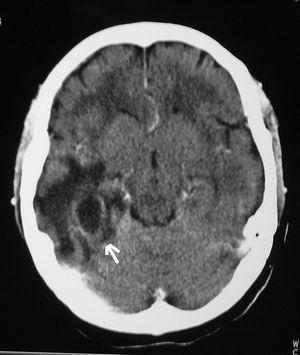

Al octavo día ingresó en la Unidad de Cuidados Intensivos en situación de coma (Glasgow Coma Scale [GCS] 5 puntos). Tras intubación y estabilización hemodinámica se realizó TAC craneal con contraste, observándose persistencia de hidrocefalia a pesar de válvula ventriculoperitoneal. La analítica de ingreso fue: hemoglobina 10,8 g/dl, leucocitos 7.200/mm3, plaquetas 225.000/mm3; sodio 147 mEq/l, potasio 6,4 mEq/l, glucemia 148 mg/dl y creatinina 4,2 mg/dl. En el LCR: hematíes 7.200 células/mm3, 400 células/mm3 l (95% polimorfonucleares), glucosa 60 mg/dl y proteínas 814 mg/dl. Se aisló, L. monocytogenes sensible a ampicilina y vancomicina. Se realizó craneotomía temporal derecha con exéresis de absceso cerebral sin retirarse la válvula ventriculoperitoneal. En el cultivo creció el mismo microorganismo. Pocas horas después el paciente presentaba GCS de 3 puntos, pupilas medias arreactivas. En la TAC craneal (fig. 2) se apreciaba ocupación ventricular por material de similar densidad que el parénquima cerebral. Se drenó material purulento semejante al evacuado del absceso por punción del reservorio de la válvula. En situación de shock séptico se objetivaron signos clínicos de muerte encefálica, que se confirmó mediante eco-doppler transcraneal. El enfermo falleció a las 24 horas de la intervención.

Figura 2. Ocupación de los ventrículos laterales.